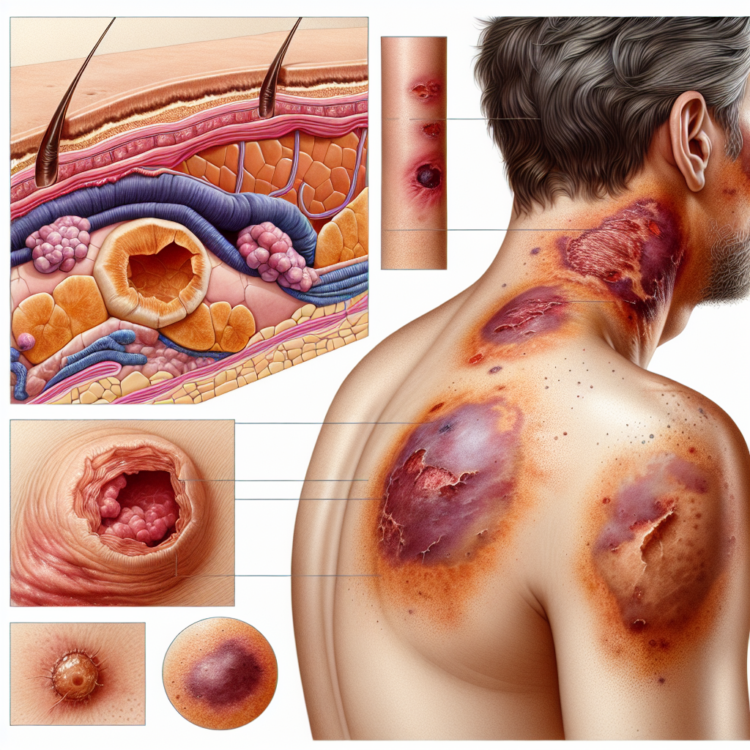

Krwiak to nagromadzenie się krwi poza naczyniami krwionośnymi, wynikające najczęściej z mechanicznego uszkodzenia tkanek. Jego powstanie często jest związane z silniejszymi urazami, które naruszają naczynia krwionośne. Może przyjmować różne formy – od małych zmian podskórnych po większe wylewy, które wymagają interwencji medycznej.

Typowe objawy krwiaka to:

- silne zaczerwienienie i obrzęk w miejscu urazu,

- ból i tkliwość tej części ciała,

- w skrajnych przypadkach – ograniczenie ruchomości w okolicy krwiaka.

Co to jest siniak?

Siniak, znany również jako stłuczenie, to powierzchniowe uszkodzenie naczyń włosowatych, które prowadzi do wycieku krwi do tkanek. W przeciwieństwie do krwiaka, siniaki są zazwyczaj mniej groźne i znikają samoistnie po kilku dniach lub tygodniach.

Oto charakterystyczne cechy siniaka:

- zmiana koloru skóry od fioletowej, przez niebieską, aż po żółto-zieloną,

- minimalny lub brak opuchlizny,

- utrzymujący się ból przy dotyku.